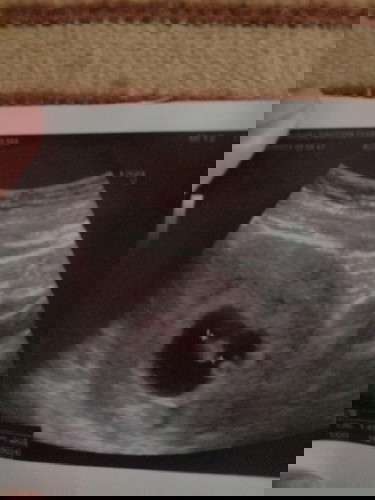

วันนี้ไปซาวด์น้องมาได้7w5dหมอบอกน้องตัวเล็กมาก

ความหมายของหมอคือ น้องอาจจะยังเล็กมากก ค่ะแต่เริ่มเป็นตัวแล้ว

เด่วก็ค่อยๆ พัฒนาค่ะ อีกหลายวีคจะเป็นหู ใบหน้า ขา แขน

อันนี้ 5-6 week ค่ะ ยังไม่เห็นตัวอ่อนเลย ตอนนี้ 31+4 แล้วค่ะ

อาหารครบ5หมู่ค่ะแต่ปกติของ7wนะคะ ของเราก็เล็กมากกก